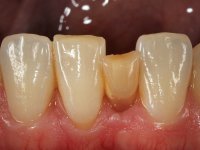

Case 2: clinical

Female patient, 40 years old, non-smoker. Presented agenesis of tooth 31 with the presence of deciduous tooth 71.

The deciduous tooth was extracted and a provisional resin crown with two small wings was bonded to the lingual surfaces of adjacent teeth. Two months later, the provisional crown was removed and the proximal walls were slightly prepared in order to parallelize the proximal walls and slight augment the mesio-distal space. After this minimal invasive dentistry, a dental impression was done with addition silicones in a one-stage technique. A provisional resin crown with an orthodontic wire on the buccal surface was then bonded to the adjacent teeth with resin, avoiding changing the prepared proximal and lingual surfaces.

Then, this Maryland bridge was bonded to the abutments.